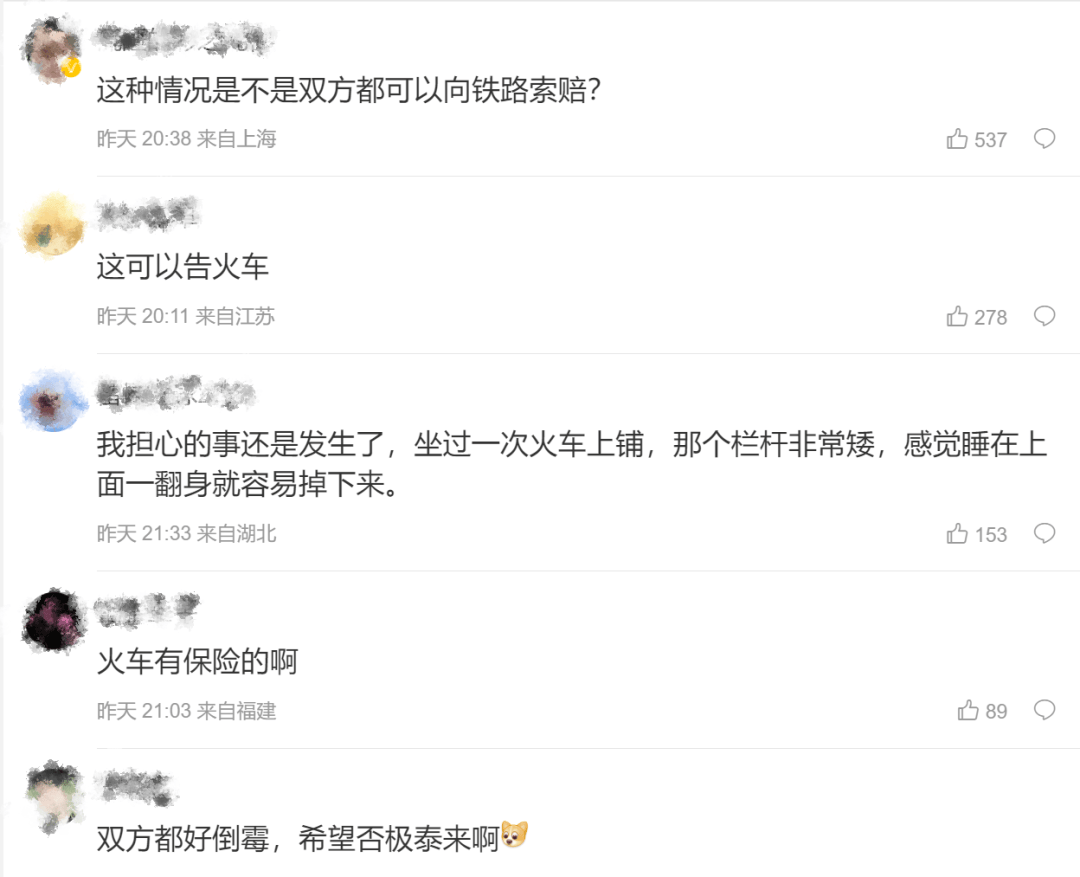

朱女士向记者出示的医院病历显示,8月24日凌晨,朱女士的女儿到医院就诊。医院诊断朱女士的女儿右股骨骨折,需要住院进一步治疗。

▲朱女士女儿手术后拍的X光片 受访者供图

朱女士出示的报警回执显示,8月24日凌晨2点22分,上海铁路公安处无锡站派出所接到报案。报案人称,在某列车上,快要到无锡站时,上铺的乘客下床时没抓稳,导致孩子大腿骨折。